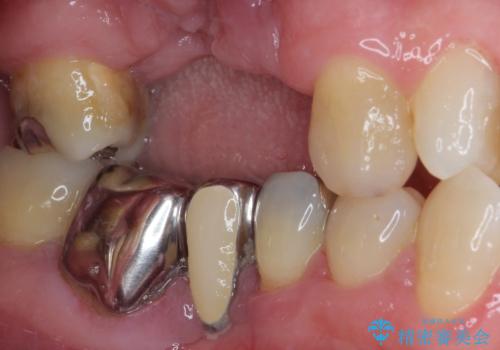

欠損の多い奥歯 インプラントによる補綴治療

- 地元ではなかなかインプラント治療を行ってくださる医院がないとのことで、転勤で東京にいる期間に治療を行いたいとのことで来院された患者様です。

上顎は左右ともに骨が少ない状態であり、特殊なドリルを用いた歯槽骨の拡大や自家骨挙上などを行いながらインプラントを埋入していくこととしました。

右下の銀歯も気になるとのことで、インプラント治療と並行してオールセラミックによるブリッジ補綴治療も行うこととしました。